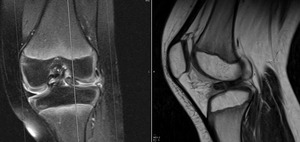

A MRI of the knee revealed a displaced tear of the anterior and posterior horns of the lateral meniscus (Figures 2 & 3).